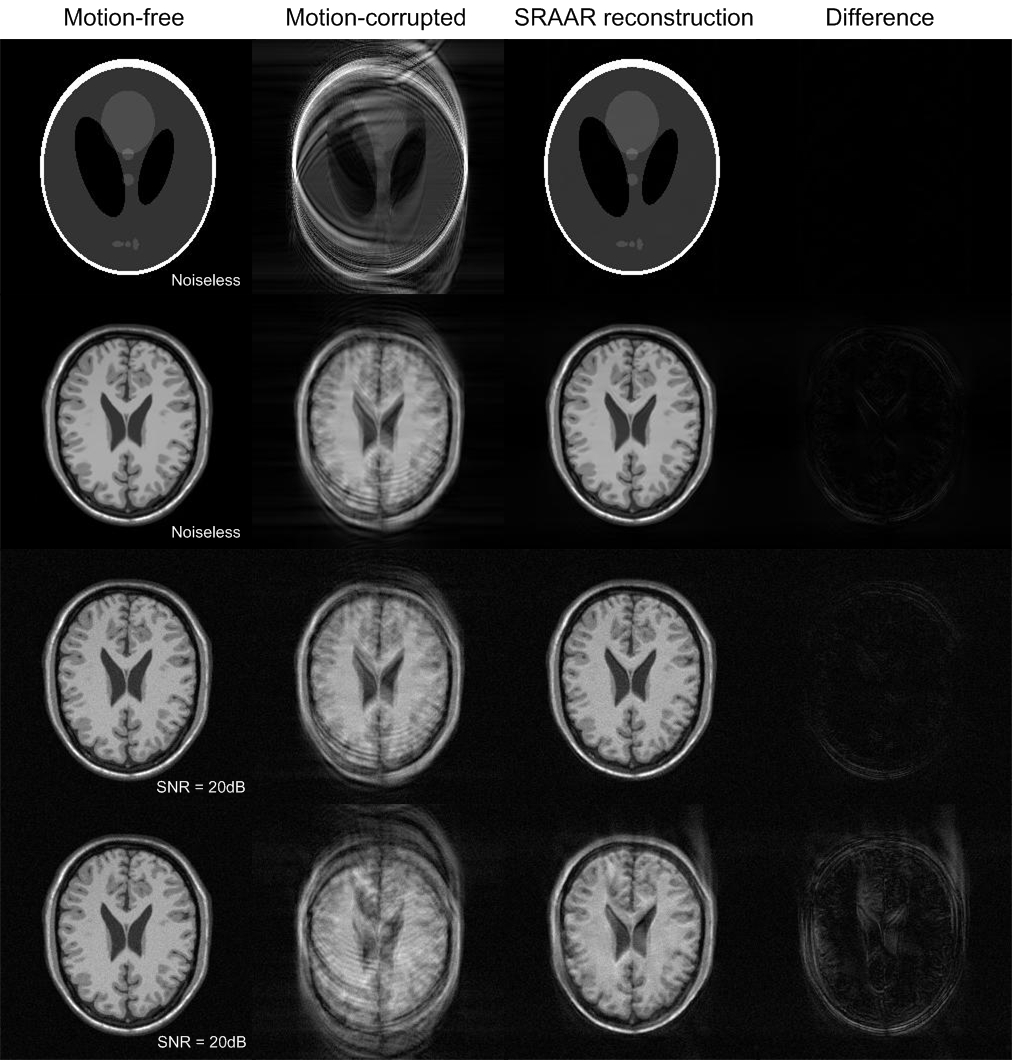

where βŠ—tensor-product\otimes denotes the circular convolution operation. So the obtained image is the true image π’Žosuperscriptπ’Žπ‘œ\boldsymbol{m}^{o} after a convolution with β„±βˆ’1β€‹πš²πœ·superscriptβ„±1subscript𝚲𝜷\mathcal{F}^{-1}\boldsymbol{\Lambda}_{\boldsymbol{\beta}}. That explains how the imaging artifacts come from the translational motion. Due to the imaging artifacts, it is natural to conjecture that the translational motion will reduce the sparsity/compressibility of MR images, i.e., the true image is the maximally sparse/compressible solution (under an appropriate basis) to (2). Examples of a Shepp-Logan phantom and simulated human brain are presented in Fig. 1. In comparison with the motion-free images (in col 1), severe artifacts are present in the motion-corrupted ones (in col 2). Numerically, it can be shown that the β„“1subscriptβ„“1\ell_{1} norms (a commonly used sparsity metric) of the motion-corrupted images (under an Haar wavelet basis) are larger than those of the motion-free ones.

The proposed method is validated using a Shepp-Logan phantom and simulated human brain data obtained from BrainWeb 111http://www.bic.mni.mcgill.ca/brainweb with both of size 256Γ—256256256256\times 256. Continuously varying translational motions among the readout lines are randomly generated. Motion artifacts are introduced by applying varying linear phase shifts to the motion-free kπ‘˜k-space data according to (1). An Haar wavelet is selected as the sparsifying transform. SRAAR is applied to the motion-corrupted kπ‘˜k-space data to reconstruct the MR images with the setting ΞΈ=0.9πœƒ0.9\theta=0.9. SRAAR is terminated after a fixed number of iterations.

Simulation results are presented in Fig. 1. For the phantom (row 1), almost exact reconstruction is obtained using SRAAR. A small amount of motions (within 5 pixels along both the readout and phase-encode directions) are studied in rows 2 (without noise) and 3 (noise added) with the human brain. It can be seen that even a small amount of motions may cause severe imaging artifacts. After the sparsity-based motion correction with SRAAR, only few artifacts remain. In the presence of both noises and a large amount of motions (as 3 times large as those in rows 2 and 3), it is shown in row 4 that SRAAR may have difficulties to produce a good result though most artifacts are removed. We note that SRAAR is computationally efficient in general. In the above, each iteration takes about 1s in Matlab v.7.7.0 on a PC with a 3GHz CPU, i.e., each reconstructed image is obtained within few minutes. Moreover, SRAAR can be greatly accelerated by estimating motions in the readout lines in parallel when computing 𝒫2subscript𝒫2\mathcal{P}_{2}.

Fig.Β 1: Simulation results of sparsity-based motion correction on a Shepp-Logan phantom (row 1, 100 iterations), simulated human brain (row 2, 200 iterations), and noisy brain with small motions (row 3, 200 iterations) and large motions (row 4, 400 iterations).